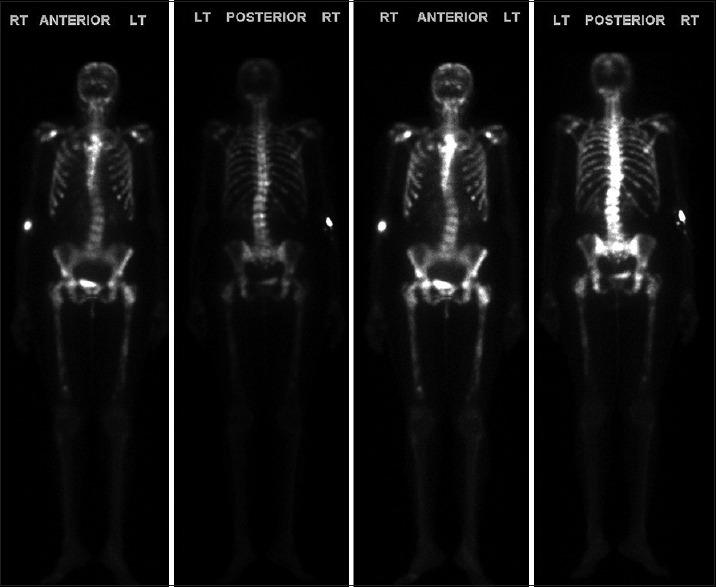

Cholangiocarcinoma (CCA) is a rare cancer of the bile duct epithelial cells and it commonly spreads to the regional lymph nodes, liver, and lungs. Bone metastasis has been reported in patients with CCA, involving both the axial and appendicular skeleton. Herein, we report a case of extrahepatic CCA with extensive bone metastases involving the calvarium, sternum, bilateral ribs and scapulae, entire spine, pelvis, and bilateral femur. To our knowledge, this is the first case report on sternum metastasis in CCA. The case presentation and review of literature highlighted the rarity of this metastasis, and health-care providers should be aware of the rare presentation of CCA.

胆管癌(CCA)是一种罕见的胆管上皮细胞癌,通常会扩散至区域淋巴结、肝脏和肺部。已有CCA患者发生骨转移的报道,累及中轴骨和四肢骨骼。在此,我们报告一例肝外CCA患者,其发生广泛骨转移,累及颅骨、胸骨、双侧肋骨和肩胛骨、整个脊柱、骨盆及双侧股骨。据我们所知,这是首例关于CCA胸骨转移的病例报告。该病例介绍及文献回顾突出了这种转移的罕见性,医疗保健人员应了解CCA的这种罕见表现。